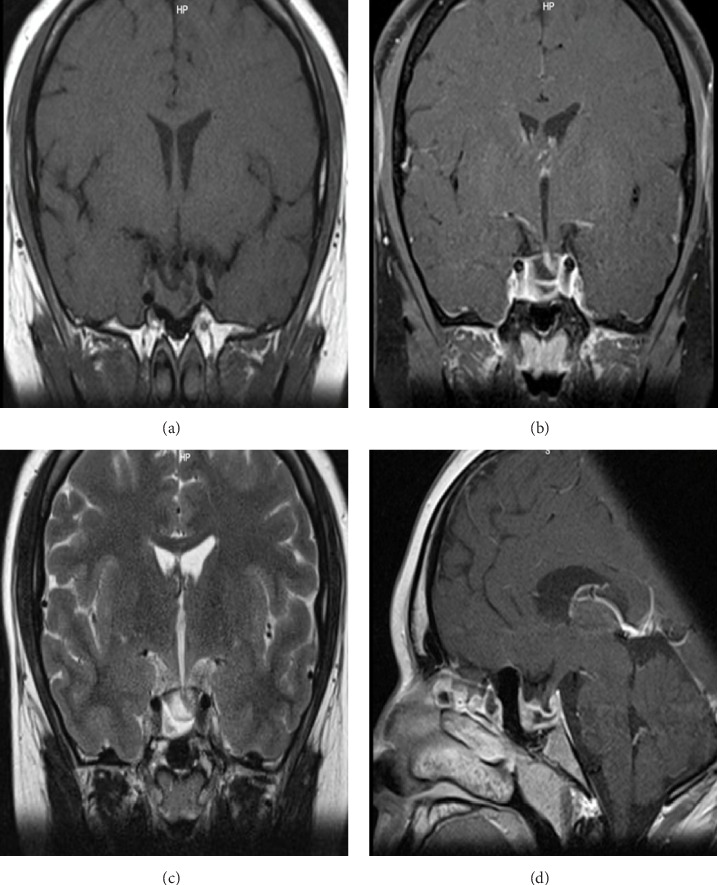

Prolactinoma is the most common pituitary tumor, with clinical presentations varying according to sex, age of onset, tumor size, and prolactin (PRL) levels. These tumors are rare in the pediatric and adolescent populations. Hyperprolactinemia leads to hypogonadotropic hypogonadism, resulting in reproductive, metabolic, sexual, and skeletal consequences that can affect puberty development. Here, we present the case of a 23-year-old male patient diagnosed with arrested puberty secondary to a macroprolactinoma. The clinical presentation, diagnostic approach, therapeutic management, and a literature review are discussed.